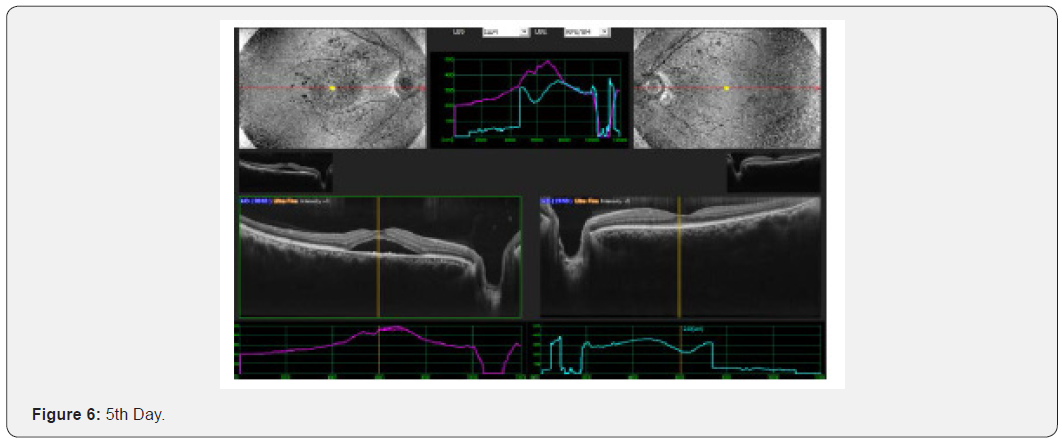

Results: This interventional study includes 21 patients who were diagnosed as acute CSC and followed from the day of presentation to 30th day. All 21 patients were undergoing intervention by using topical bromfenac eye drop, one drop twice daily for 30 days. Macular thickness and visual acuity recorded from the day of presentation up to 30th day. (Table 6) shows all changes before and after treatment and (Figure 1-4) shows early resolution of sub-macular fluid in one of these patients treated with topical bromfenac eye drops (one drop twice daily). In group 1 the macular thickness (CFT) improve from 422-485 microns at onset to 317-382 microns on 5th day becomes 246-295 on 10th day while 210-226 on 30th day. Vision improved from 0.4 to 0.7 at 5th day, improved to 0.8 on 10th day and remained same on 30th day. In group 2 the CFT reduced from 535-565 microns to 401-440 microns on 5th day becomes 318310 on 10th day and on 30th day it was 221-232 microns with improvement in visual acuity which was 0.2 at onset to 0.6 at 5th day, 0.7 at 10th day and improved to 0.8 on 30th day. In group 3 the CFT reduced from 657-722 microns to 456-469 microns on 5th day, 259-366 microns on 10th day while 206-227 microns on 30th day. Visual acuity improved from CF at onset to 0.4 on 5th day, 0.6 on 10th day and improved to 0.7 on 30th day. Conclusion: This, simple, safe, affordable and easily available treatment modality in all parts of the world with early rehabilitation of acute CSC patients.

This interventional retrospective as well as prospective study includes 21 patients who were diagnosed as acute CSC and followed from the day of presentation to 30th day. All 21 patients were undergoing intervention by using topical bromfenac eye drop, one drop twice daily for 30 days. Macular thickness and visual acuity recorded from the day of presentation up to 30th day. (Table 6) shows all changes before and after treatment and (Figure 1-8) shows early resolution of sub-macular fluid in one of these patients treated with topical bromfenac eye drops (one drop twice daily). In group 1 the macular thickness (CFT) improve from 422-485 microns at onset to 317-382 microns on 5th day becomes 246-295 on 10th day while 210-226 on 30th day. Vision improved from 0.4 to 0.7 at 5th day, improved to 0.8 on 10th day and remained same on 30th day. In group 2 the CFT reduced from 535-565 microns to 401-440 microns on 5th day becomes 318-310 on 10th day and on 30th day it was 221-232 microns with improvement in visual acuity which was 0.2 at onset to 0.6 at 5th day, 0.7 at 10th day and improved to 0.8 on 30th day. In group 3 the CFT reduced from 657-722 microns to 456-469 microns on 5th day, 259-366 microns on 10th day while 206-227 microns on 30th day. Visual acuity improved from CF at onset to 0.4 on 5th day, 0.6 on 10th day and improved to 0.7 on 30th day.